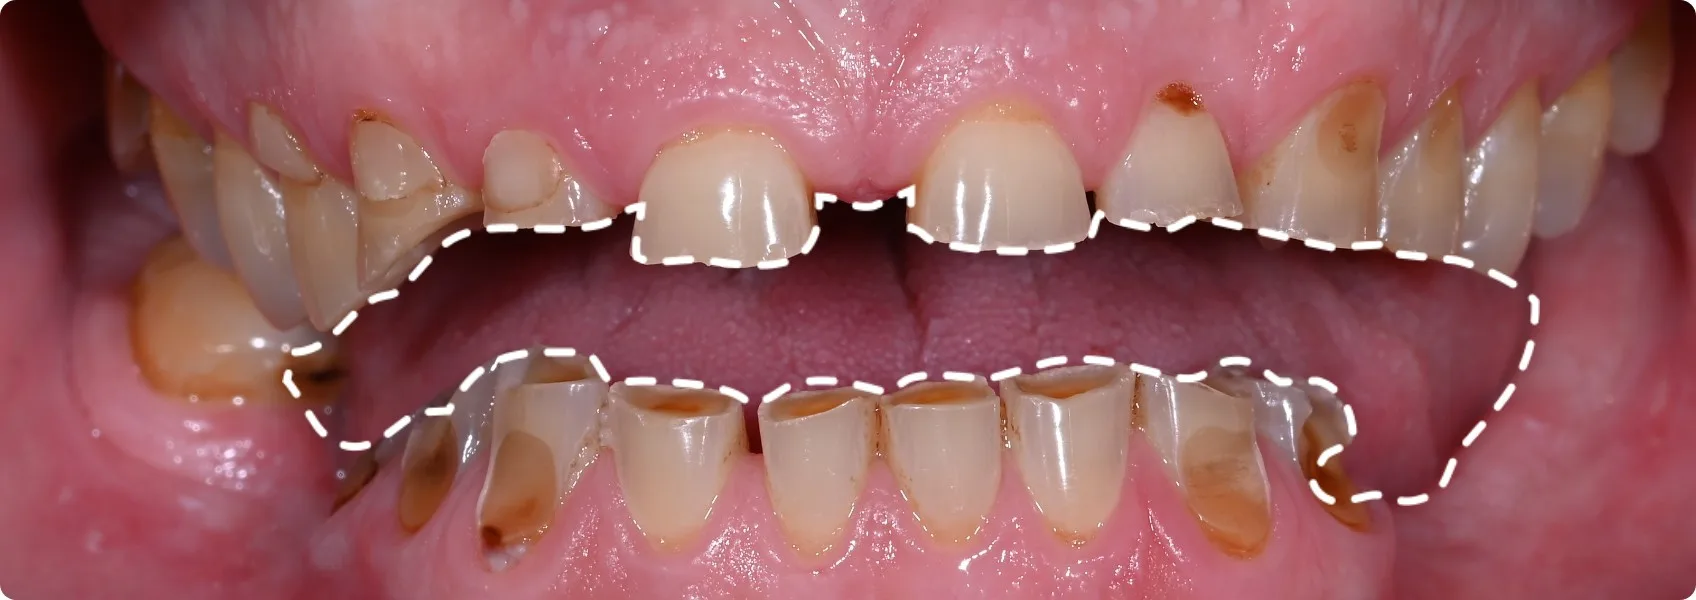

Pacjent trafił do nas z mocno zaburzonym zgryzem — i bólem.

Zęby były nie tylko bardzo mocno starte, ale brakowało też wielu z nich w dolnym łuku. Relacja między górnymi a dolnymi zębami była tak zaburzona, że Pacjent de facto nie posiadał prawidłowego zgryzu!

To rodziło codzienne trudności: problemy z gryzieniem, żuciem, a nawet mówieniem. Dodatkowo potęgował się ból w stawie skroniowo-żuchwowym. Lek. dent. Adrian Złotogórski zakwalifikował Pacjenta do pełnej rekonstrukcji zgryzu. To była jedyna droga do odzyskania komfortu i funkcji.

Zanim mogliśmy myśleć o odbudowie, musieliśmy dokładnie zbadać każdy ząb i przygotować solidne podstawy pod przyszłą pracę protetyczną.

Najpierw dokładnie przeanalizowaliśmy i przygotowaliśmy fundamenty pod rekonstukcję. Zaczęliśmy od diagnostyki i analizy zdjęć RTG.